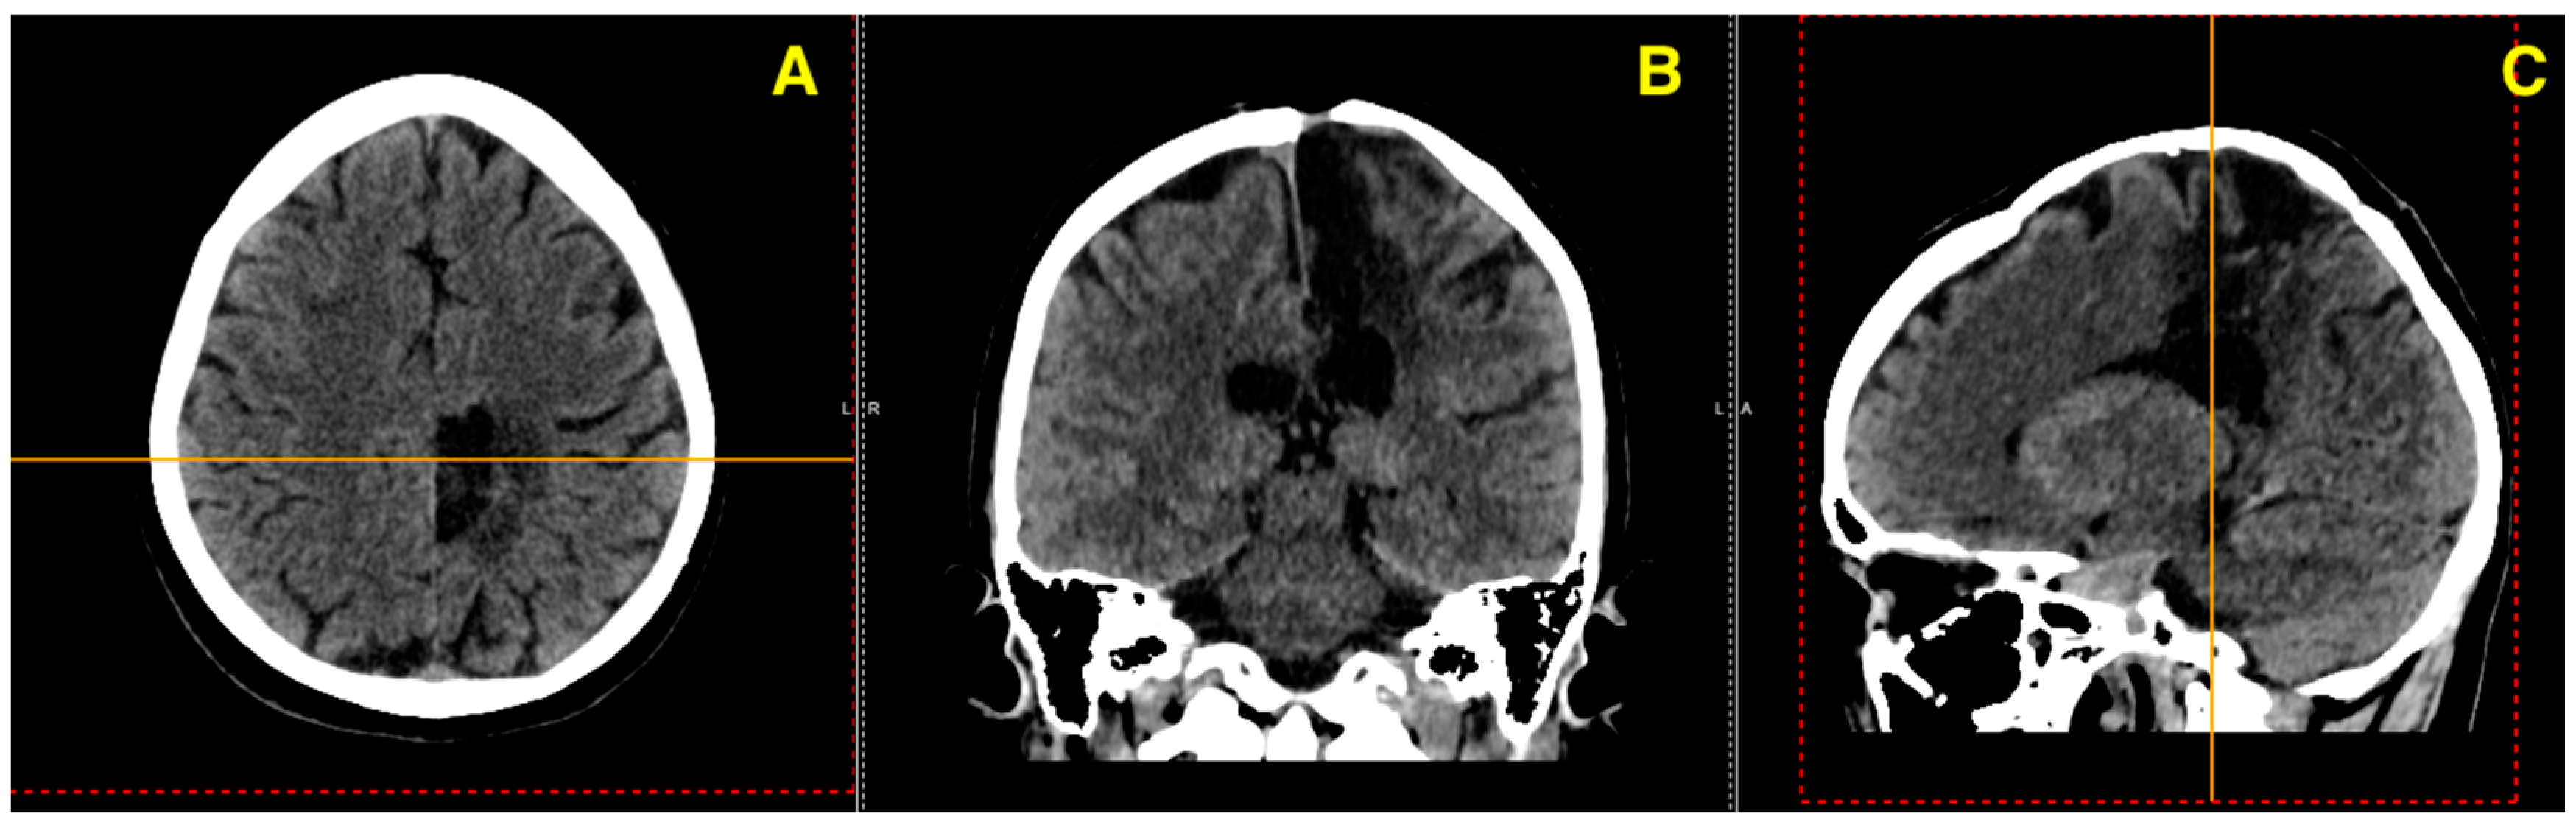

Challenging Management of a Rare Complex Cerebral Arteriovenous Malformation in the Corpus Callosum and Post-Central Gyrus: A Case Study of a 41-Year-Old Female

2. Case Presentation